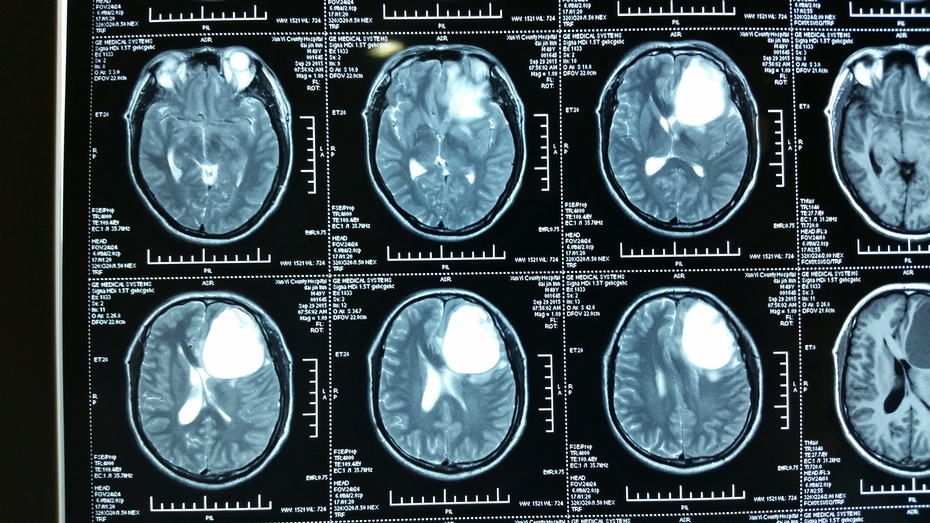

胶质瘤手术一例

高级别胶质瘤的扩大切除 - 好大夫在线

mri:考虑胶质瘤,不除外转移瘤.

分享一例左侧颞叶星形胶质瘤的核磁影像

mri:右额占位,考虑胶质瘤.

颞叶内侧恶性胶质瘤

左额叶占位胶质瘤可能

右额叶巨大占位胶质瘤可能

上皮样胶质母细胞瘤一例(2018华东胶质瘤mdt病例二)--浙二神外周刊(第

脑干胶质瘤的影像表现 - 好大夫在线